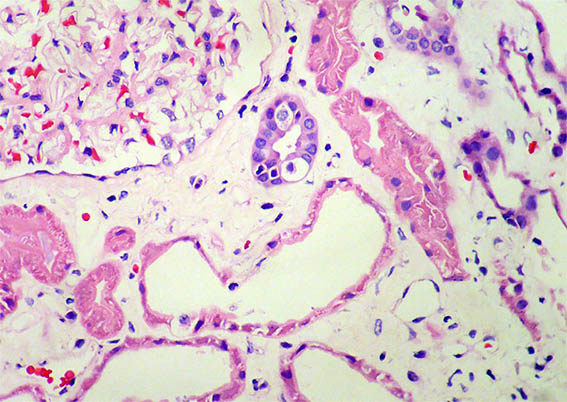

Figura 4. H&E, X400.